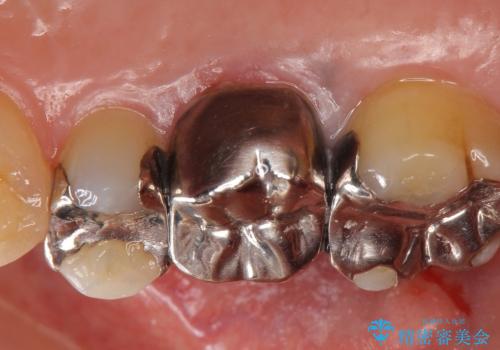

- 右上6番目の銀歯と歯茎の間に隙間ができているのが気になるので診て欲しいといらっしゃった方の症例です。

根管治療も希望されたため、再根管治療終了後、オールセラミッククラウンによる補綴を行いました。